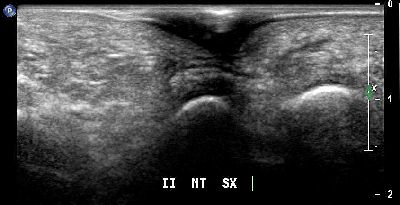

Calcificazione intra articolare (img. 01) Calcificazione intra articolare 01

Calcificazione intra articolare (img. 02) Calcificazione intra articolare 02

Calcificazione intra articolare (img. 03) Calcificazione intra articolare 03